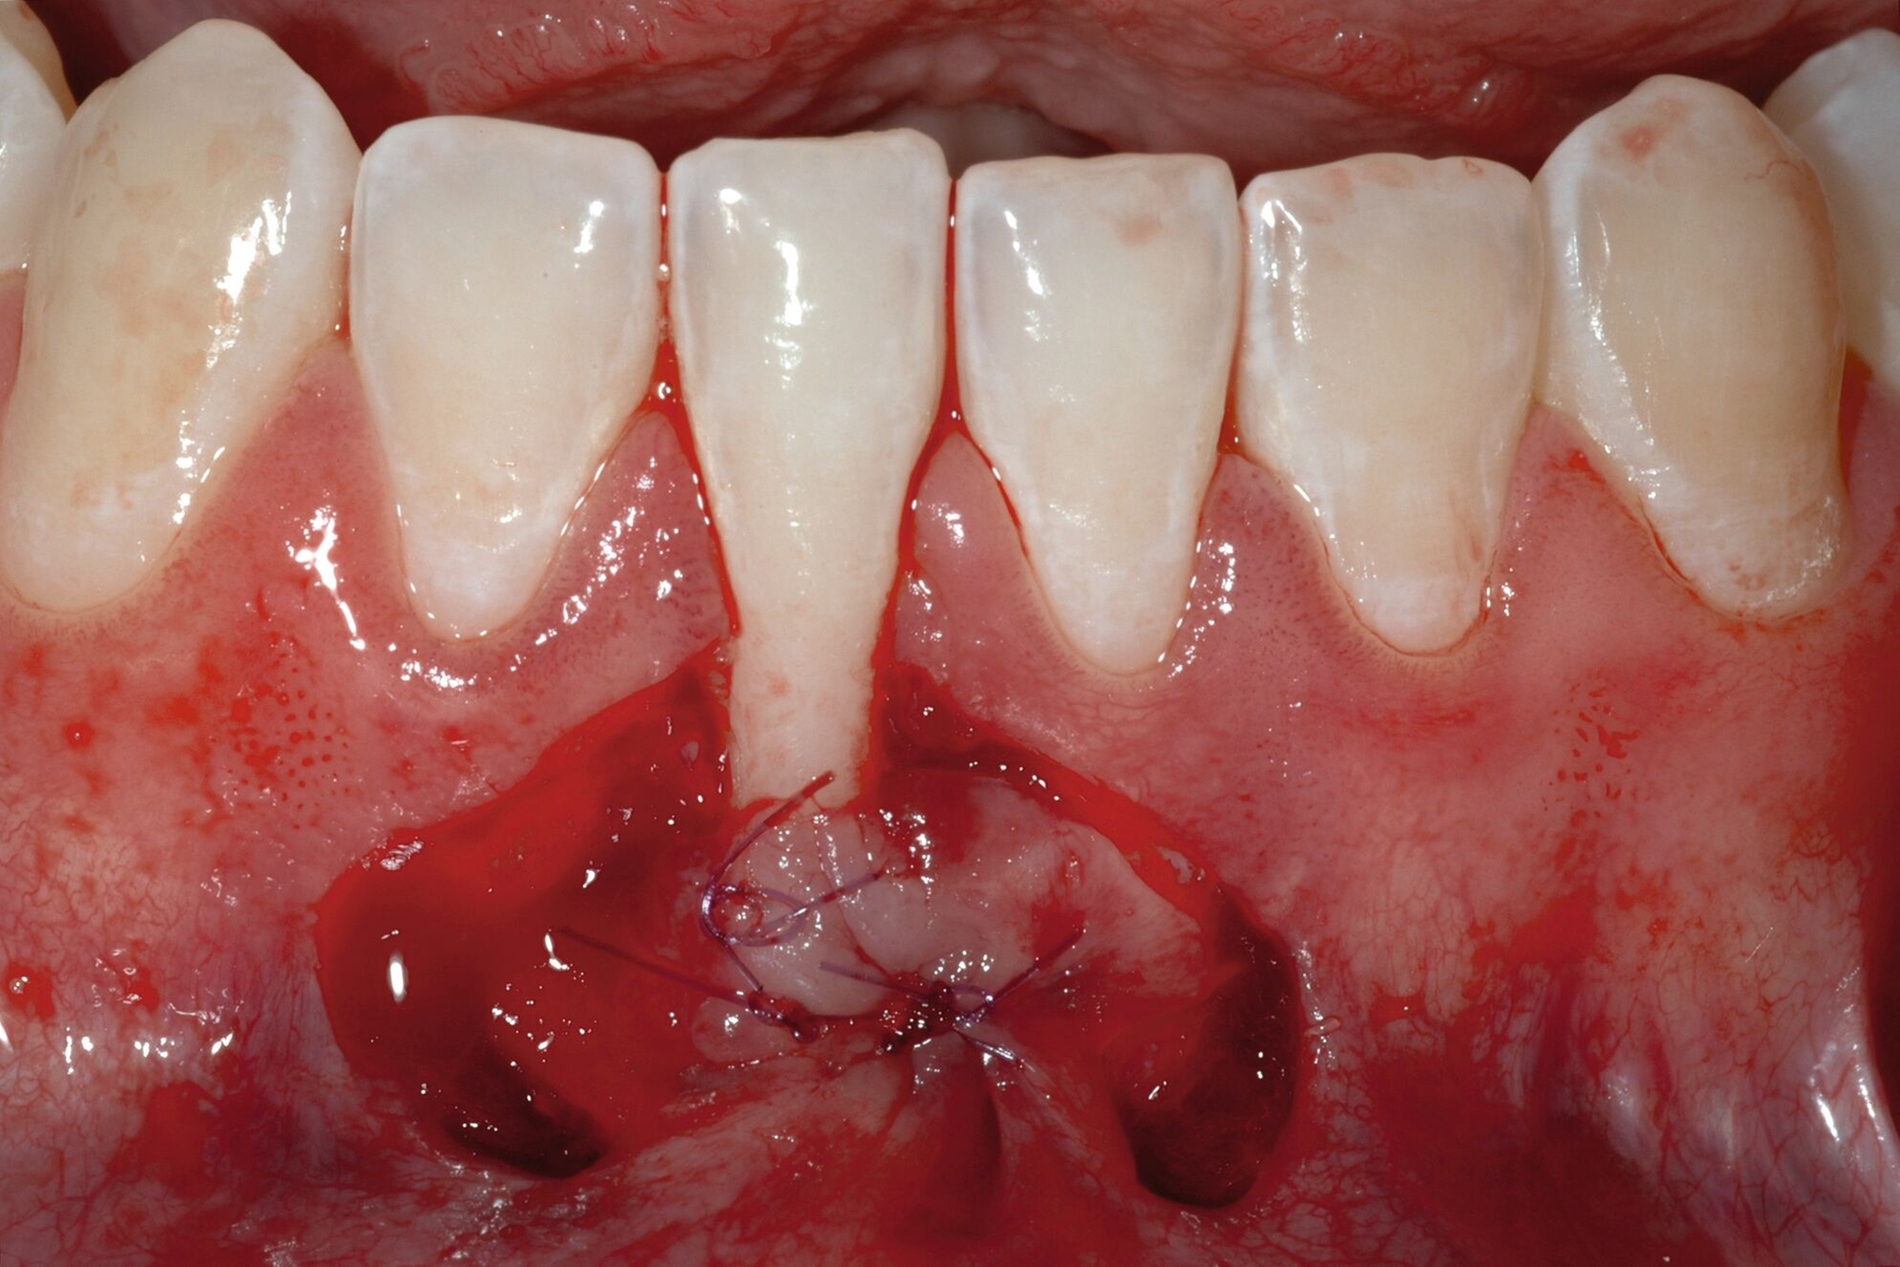

Tunkel et al. versuchten die Vorteile von Zucchellis Koronalem Verschiebelappen und Sculeans Lateral Geschlossenem Tunnel in einer Technik zu vereinen: dem Lateral Geschlossenen Koronalen Verschiebelappen (LCAF) [Tunkel et al., 2024] (Abbildung 3). Bei dieser Methode, mit der vor allem tiefe singuläre parodontale Rezessionen behandelt werden, wird die Koronalverschiebung ohne Entlastungsinzisionen kombiniert mit dem lateralen Verschluss der tiefen parodontalen Rezession.

Das Vorgehen ist hier wie folgt: Zunächst wird im Bereich der tiefen Rezession der Gingivarand geringfügig exzidiert, um ein Zusammenwachsen der geschlossenen Lappenanteile zu ermöglichen. Anschließend wird der Schnitt in horizontaler Richtung durch leicht bogenförmige Schnittführungen auf Höhe der Schmelz-Zement-Grenze erweitert, um mindestens zwei Zähne rechts und links von der Rezession (Abbildung 3b). Im Unterkiefer-Frontzahnbereich, wo die Rezessionen heutzutage am häufigsten vorkommen, sollte der Lappen mindestens von Eckzahn zu Eckzahn gebildet werden, um ein harmonisches Ergebnis nach Abheilung zu erreichen. Auf vertikale Entlastungsinzisionen kann komplett verzichtet werden. Anschließend erfolgt die Lappenpräparation nach dem bereits für koronale Verschiebelappen gängigen Prinzip teilschichtig-vollschichtig-teilschichtig.

Die Papillenbereiche werden mit dem Skalpell scharf vom Periost abgelöst. Dann wird das Periost durchtrennt und bis zur mukogingivalen Grenze ein vollschichtiger Lappen gebildet. Nach Überschreiten dieser wird wieder zweischichtig präpariert. Hierdurch wird eine gute Mobilisation des Lappens erreicht, die eine ausreichende Koronalverschiebung ermöglicht. Entgegen dem in früheren Jahren propagierten komplett teilschichtigen Vorgehen, kann durch dieses Verfahren die Gefahr von Lappenperforationen signifikant gesenkt werden, da diese insbesondere im Bereich der mukogingivalen Grenze auftreten. Nachdem die Lappenareale mesial und distal der Rezession gelöst sind, können diese durch zwei bis drei feine monofile Nähte miteinander verbunden werden (Abbildung 3c). Sobald durch diese Naht ein zusammenhängender koronaler Verschiebelappen entstanden ist, werden die Papillenbereiche koronal des gebildeten Lappens entepithelialisiert. Nach Entnahme eines Bindegewebstransplantats oder entepithelialisierten freien Schleimhauttransplantats wird die Wurzeloberfläche mit EDTA-Gel konditioniert und anschließend werden Schmelz-Matrix-Proteine aufgetragen (Abbildung 3d). Diese bewirken die Bildung eines new attachment und fördern zudem die Wundheilung, was gerade bei den delikaten lateralen Verschiebelappen von Vorteil sein sollte [McGuire und Cochran, 2003; Almqvist et al., 2011; Thoma et al., 2011; McGuire et al., 2016]. Anschließend wird das Transplantat durch Nähte ausgehend vom oralen Papillenbereich fixiert (Abbildung 3e). Zuletzt wird der Lappen mit sogenannten doppelten Umschlingungsnähten im Bereich der Papille durch Zug nach koronal und oral fixiert, was eine perfekte Positionierung ermöglicht [Zuhr et al., 2009] (Abbildung 3f). Hierbei muss darauf geachtet werden, dass der Lappen die Schmelz-Zement-Grenze um mindestens 2 mm überdeckt, um eine hundertprozentige Wurzeldeckung erwartbar zu machen [Pini Prato et al., 2005].

Der Lateral Geschlossene Koronal Verschobene Lappen ermöglicht eine annähernd narbenfreie Deckung singulärer parodontaler Rezessionen durch Verzicht auf vertikale Entlastungsinzisionen (Abbildung 3g). Das Lösen der Papillen im Rahmen der Verschiebung ermöglicht eine deutliche Anhebung des Lappens und somit durch großzügige Überdeckung das Erreichen vollständiger Wurzeldeckungen. Durch den lateralen Verschluss im Rahmen der tiefen, über die mukogingivale Grenze hinausgehenden Rezession kann keratinisierte Gingiva im Bereich dieser hergestellt und eine übermäßige Mobilisation und damit Einschränkung des Vestibulums verhindert werden.